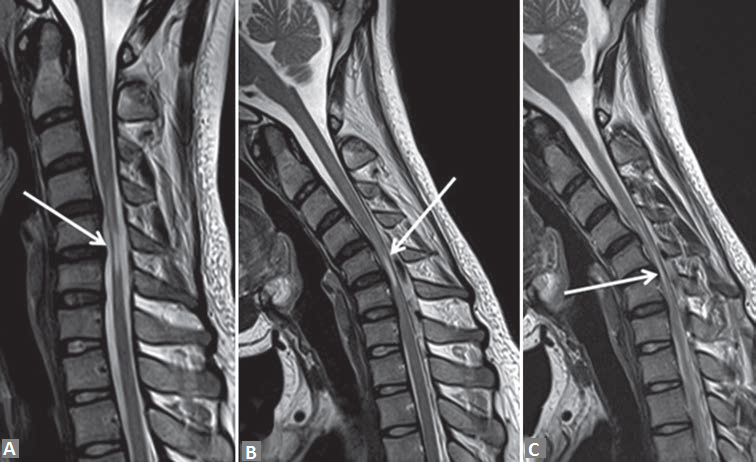

The cervical spine radiographs were normal. Routine magnetic resonance image (MRI) [Figure 1a] revealed spinal cord atrophy from C4-C5 to C6-C7 disc levels, but without history of trauma or ischemic insult and with no evidence of compressive lesion or osteophyte, cord atrophy appeared nonspecific. Thinning of the spinal cord is evident as reduction in the anteroposterior diameter of the spinal cord with myelomalacia more prominent in right hemicord [Figures 1a, 3a and 3b].

Given the young age of patient and focal spinal cord atrophy, a dynamic evaluation of the cervical spine with flexion and extension was performed. MRI during neck flexion on T2-weighted images [Figure 1b and c] revealed anterior displacement of the posterior dura with epidural flow voids and compression of the spinal cord. Flexion pre and postcontrast T1 MRI in midline sagittal plane [Figure 2a and b] revealed enhancement in posterior epidural space suggestive of enhancement of epidural plexus. Axial postcontrast T1 flexion MRI [Figure 3c and d] demonstrates thinning of the spinal cord, more prominent in right hemicord with posterior epidural enhancement. On extension in postcontrast T1 [Figure 2c], the posterior epidural space and its enhancement disappeared consequent to posterior displacement of posterior dura, also the cord compression was relieved.